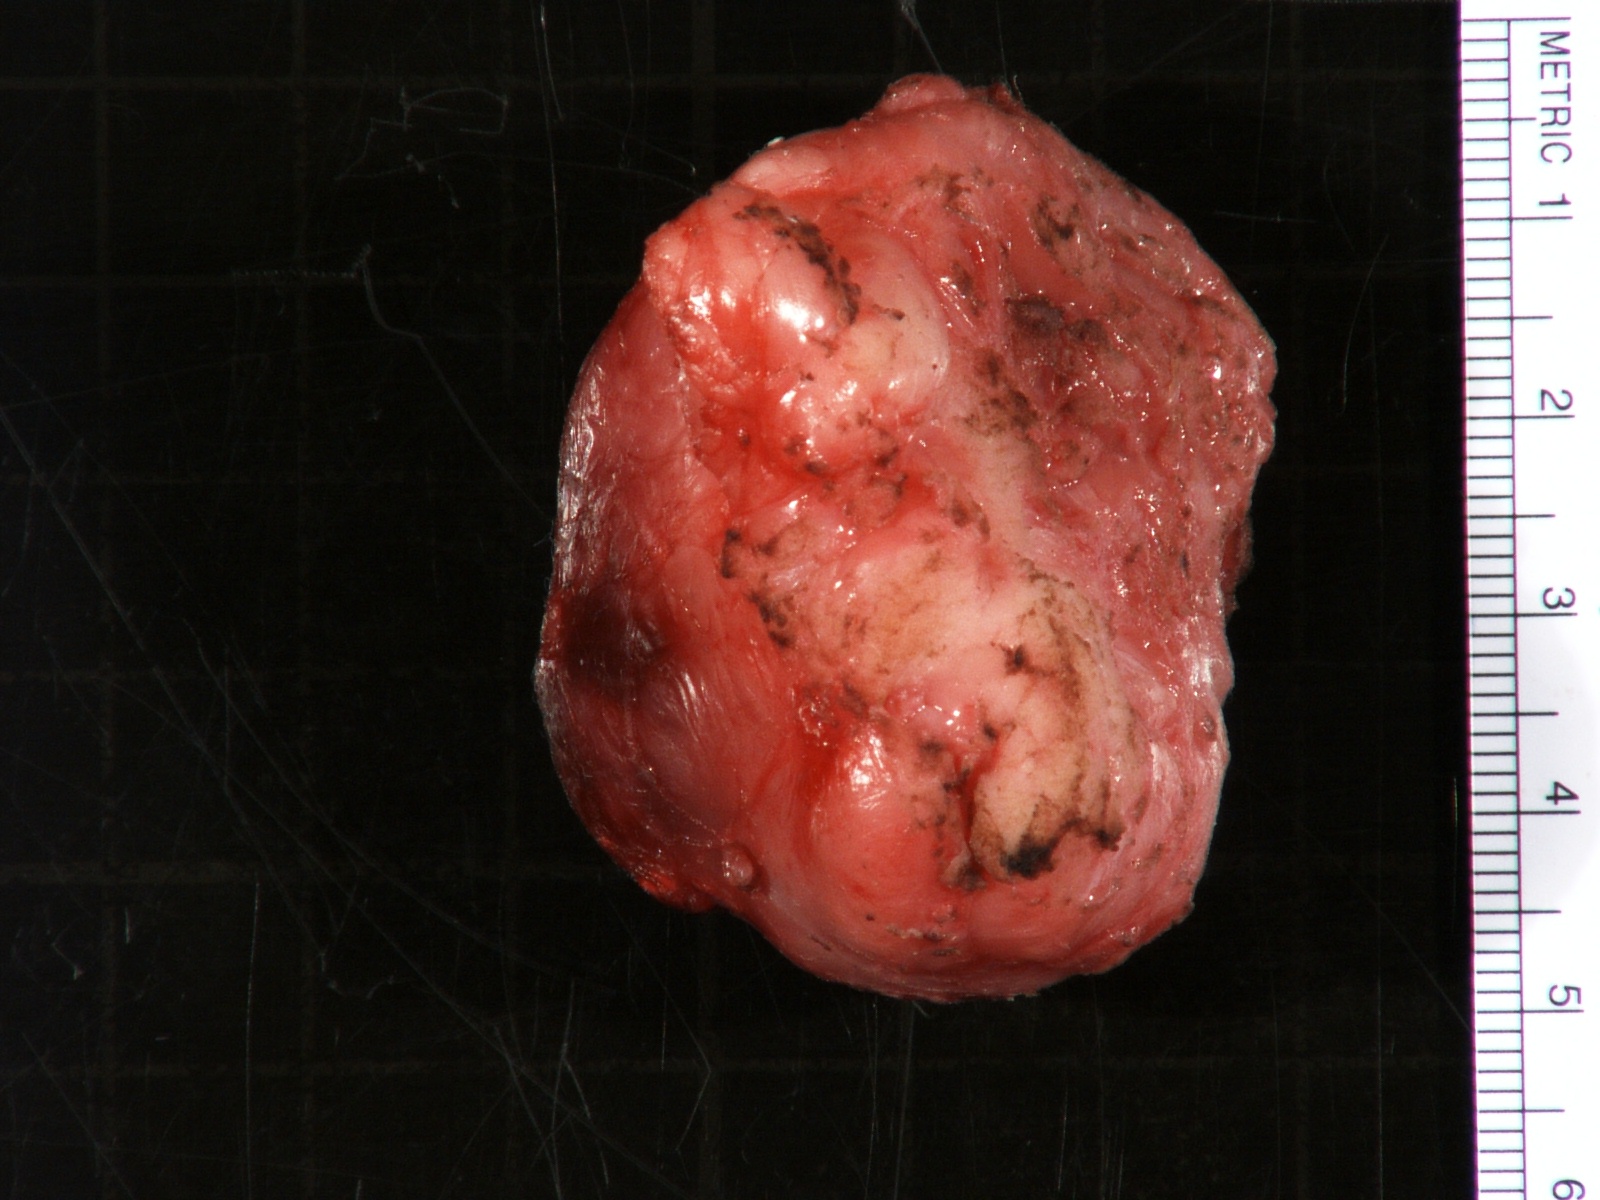

- More homogeneous and mature appearance than neuroblastoma

- Varies by subtype, from circumscribed ovoid mass to large multilobulated tumor

- Stroma rich, nodular subtype: area(s) of stroma poor, immature tumor are usually hemorrhagic with well defined borders (J Natl Cancer Inst 1984;73:405)

- Calcification (chalky white, yellow areas) and cystic degeneration may occur

- If large, adrenal gland may be difficult to identify